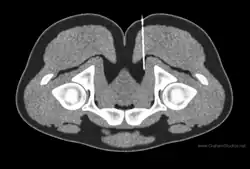

Diagnostic nerve blocks can confirm the clinical diagnosis for chronic pain as well as identify the entrapment site.[5] A diagnostic block is like an inverted palpation in the sense that palpation will cause a sensory nerve to send a signal (action potential) and a block will prevent a sensory nerve from sending a signal. By blocking nerve signals, the pain-contributing nerves can be identified or ruled out. Nerves are predisposed to entrapment in certain anatomical regions such as in an osteofibrous tunnels, through a muscle, adjacent to fibrous tissue.[6] Consequently, knowledge of these anatomical regions as well as peripheral nerve anatomy is an essential component to planning successful diagnostic blocks.[5] Ultrasound is a common form of image-guidance to place the needle properly, but it faces limitations visualizing small and deep nerves.[7] CT- or MRI- guidance are better positioned to access deep nerves as well as identify the anatomic level of the needle.[7]

MRI may be used to identify certain causes of entrapment such as a structural lesions pressing on a nearby nerve, but is prone to false negatives/positives and has poor correlation with the clinical examination.[8] A major limitation with MRI is that nerve tissue is resistant to imaging. An advancement of MRI that takes advantage of the tissue properties of nerves, called MR neurography (MRN), provides more detail. MR tractography (MRT) can also be of use in surgical planning as it can identify peripheral nerve abnormalities with a high correlation to intraoperative findings and has higher accuracy than MR neurography alone.[9] MRT uses diffusion tensor imaging to visualize the directional movement of water molecules along nerve tracts. Often an abnormality can be identified along tracts of nerve where water is not diffusing normally along the axis. MRT has been used to identify sacral nerve entrapment by the piriformis muscle, which would otherwise only be diagnosable with exploratory surgery.[10]